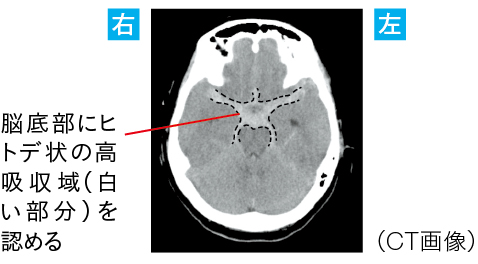

●CT画像により、脳底動脈瘤の破裂がくも膜下出血を招き、髄膜刺激症状による頭痛が発生していると考えられた

頭蓋内病変による頭痛のなかで最も代表的なものはくも膜下出血です。くも膜下出血による頭痛は、発症時より認められることが特徴です。なお、それ以外の頭蓋内疾患(脳出血、脳梗塞、脳腫瘍)では、頭痛が初期から認められることは多くありません。

1)くも膜下出血による頭痛

くも膜下出血による頭痛は、頭蓋内圧亢進症状と髄膜刺激症状が考えられます(頭蓋内で痛覚を有するのは血管と硬膜の一部であり、脳実質では疼痛を感じることはありません)。

くも膜下腔に流れ込んだ血液により、頭蓋内の容積が増え、頭蓋内圧が亢進することによって、痛覚を有する血管が直接刺激され圧迫されることで、頭痛が引き起こされます。悪心・嘔吐、けいれん、意識障害を伴うことがあります。